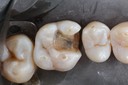

Kyle Chock #14 prep